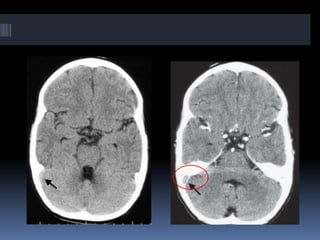

FLAIR (left) and GRE (right) in the same case show HT in this example of subacute

stroke